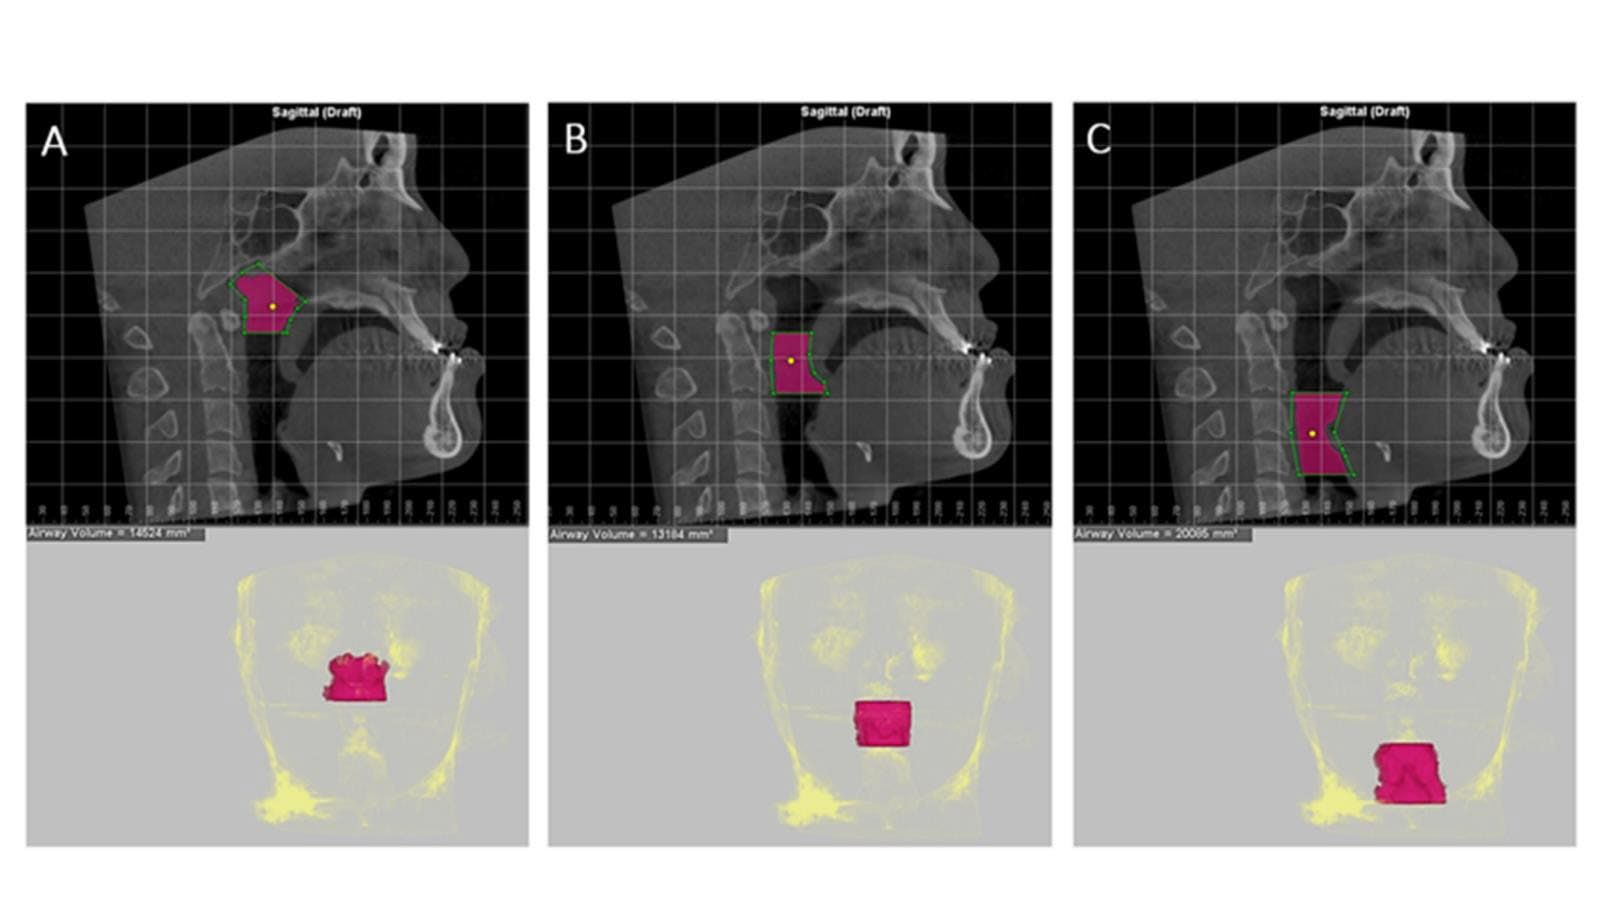

Midsagittal CBCT images were selected. Maxillary and mandibular movement was measured in mm using the difference in the distance from points A (Maxillary movement) and point B (Mandibular movement) to the Na‒PP plane at each time point (Figure 2). For airway analysis, the pharyngeal airway was divided into 3 levels according to Park’s protocol (Park et al., 2012), the nasopharynx (NP; between the PNS-V plane and CV1 plane), oropharynx (OP; between the CV1 and CV2 planes), and hypopharynx (HP; between the CV2 and CV4 planes) (Figure 3). The airway volume at each level was analyzed using the Sinus/Airway tool in Dolphin software. The area of interest was manually outlined at each airway level (NP, OP and HP) as previously described. Then, the threshold value was selected to fill the degree of airway at a detection sensitivity of 70% and the airway volume was automatically calculated in mm3. The excess selected area was manually selected from the axial and coronal CBCT images at the corresponding level (Figure 4). Airway measurements were made at T0, T1 and T2. A generalized linear model with repeated measures analysis was used to identify significant differences in airway volume among the three time points, with a P value less than 0.05 considered to indicate statistical significance. To eliminate confounding factors of the baseline volume, the altered airway volume was calculated as a percentage change before prediction analysis (Brunetto et al., 2014). The skeletal relapse was defined as the anteroposterior change in the position of the A-point or B-point from the immediate postoperative (T1) to the 6-month postoperative (T2) time point.

Figure 4. Measurement of the pharyngeal airway volume at 3 levels. The green lines indicate the airway level boundaries, while the purple area indicates the designated region of interest; the threshold value selected was 70%. The morphology of the airway was determined as follows. A: Nasopharynx. B: Oropharynx. C: Hypopharynx.